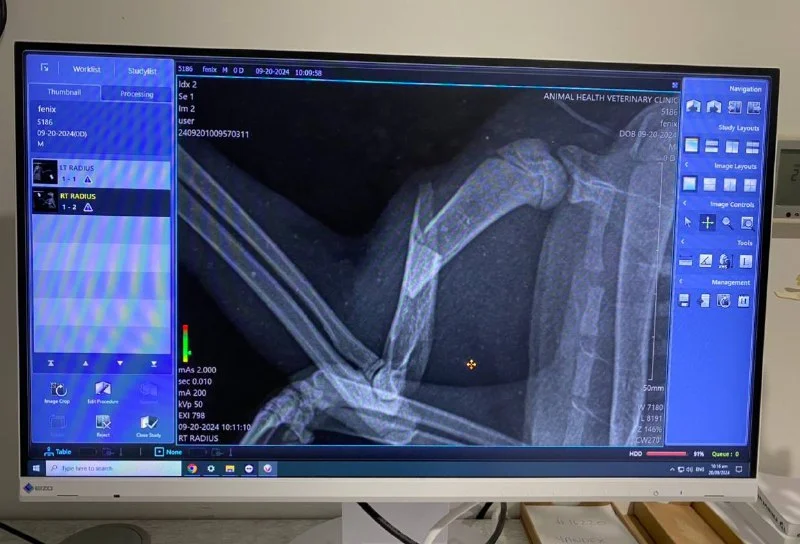

Здравствуйте! Срочно ищем семью или передержку хотя бы на две недели… нашла Зайку в кустах с перебитой лапой. Благодаря отзывчивым людям из чата животных Кипра - была собрана вся необходимая сумма на операцию. Зайку прооперировали в пятницу и оставили до понедельника в стационаре. Дальше нам идти некуда … 💔 ей нужно ограничить движение, давать 10 дней антибиотики и болеутоляющие, и вынуть спицу через 14 дней…